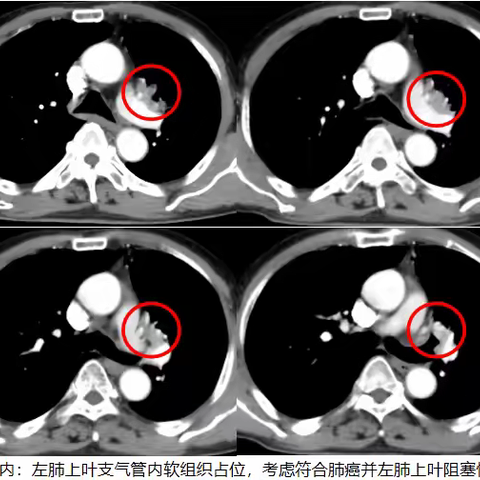

“米粒神奇立大功”!肺癌肿瘤神奇“蒸发”,粒子植入术让癌症患者重获新生!